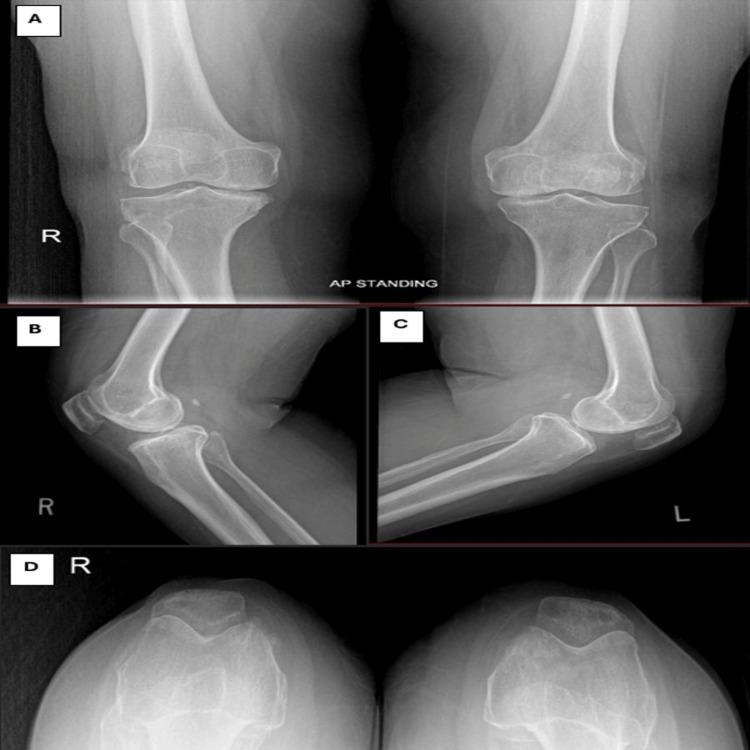

Total knee arthroplasty (TKA) is a common procedure for managing severe knee osteoarthritis. However, component loosening continues to be a common issue, frequently requiring revision surgery. Although the medial parapatellar (MPP) approach is commonly used due to the broad access it provides, it may disrupt the extensor mechanism and reduce blood flow to the patella. We present a case of a 62-year-old woman who required revision TKA (RTKA) on the left knee due to tibial component loosening seven years after her initial surgery, which had been performed via the MPP approach. We have used the midvastus (MV) approach to preserve the quadriceps tendon. This case highlights the MV approach as a viable alternative in RTKA, offering adequate exposure while minimizing soft tissue damage.

全膝关节置换术(TKA)是治疗重度膝关节骨关节炎的常见手术。然而,假体松动仍然是一个常见问题,常常需要进行翻修手术。尽管内侧髌旁(MPP)入路因其提供的广泛视野而被广泛使用,但它可能会破坏伸膝机制并减少髌骨的血液供应。我们报告一例62岁女性病例,该患者在初次手术(采用MPP入路)七年后,因胫骨假体松动需要对左膝进行翻修全膝关节置换术(RTKA)。我们采用股中肌(MV)入路以保留股四头肌肌腱。该病例突出了MV入路在RTKA中作为一种可行替代方法的优势,它能提供足够的视野,同时将软组织损伤降至最低。